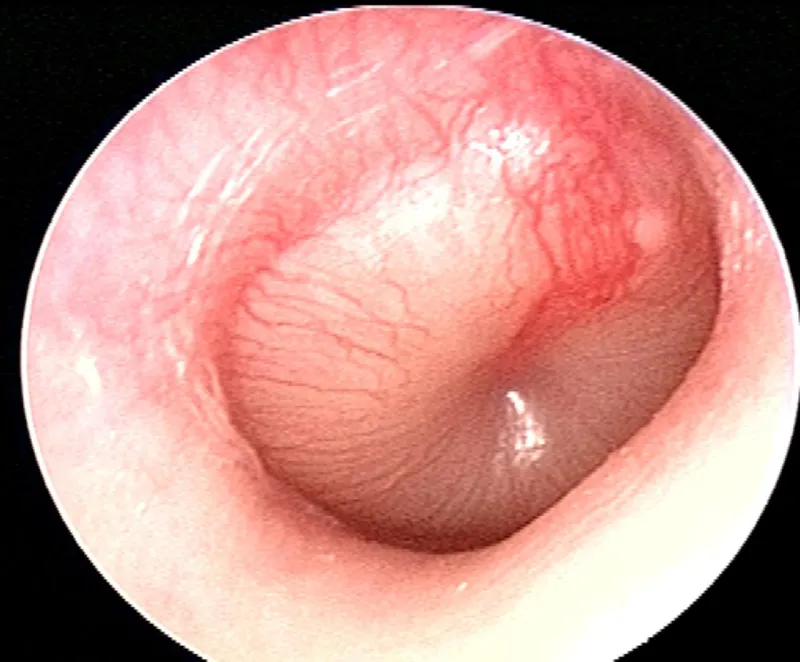

| Tympanic membrane | Translucent, mobile | Perforation, hemotympanum | ENT consultation |

⭐ Clinical Pearl: The "Emergency Audiometry Triangle" - Weber lateralization to affected ear + negative Rinne + visible tympanic membrane abnormality = 95% probability of surgically correctable conductive hearing loss requiring urgent ENT consultation.